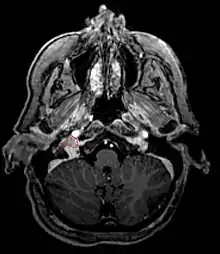

• Commonly arise from the paraganglia of the jugular bulb

• Typically invade the tympanic cavity and jugular foramen

• Can extensively invade petroclival region

• Can invade cavernous sinus above

• Can invade hypoglossal canal below